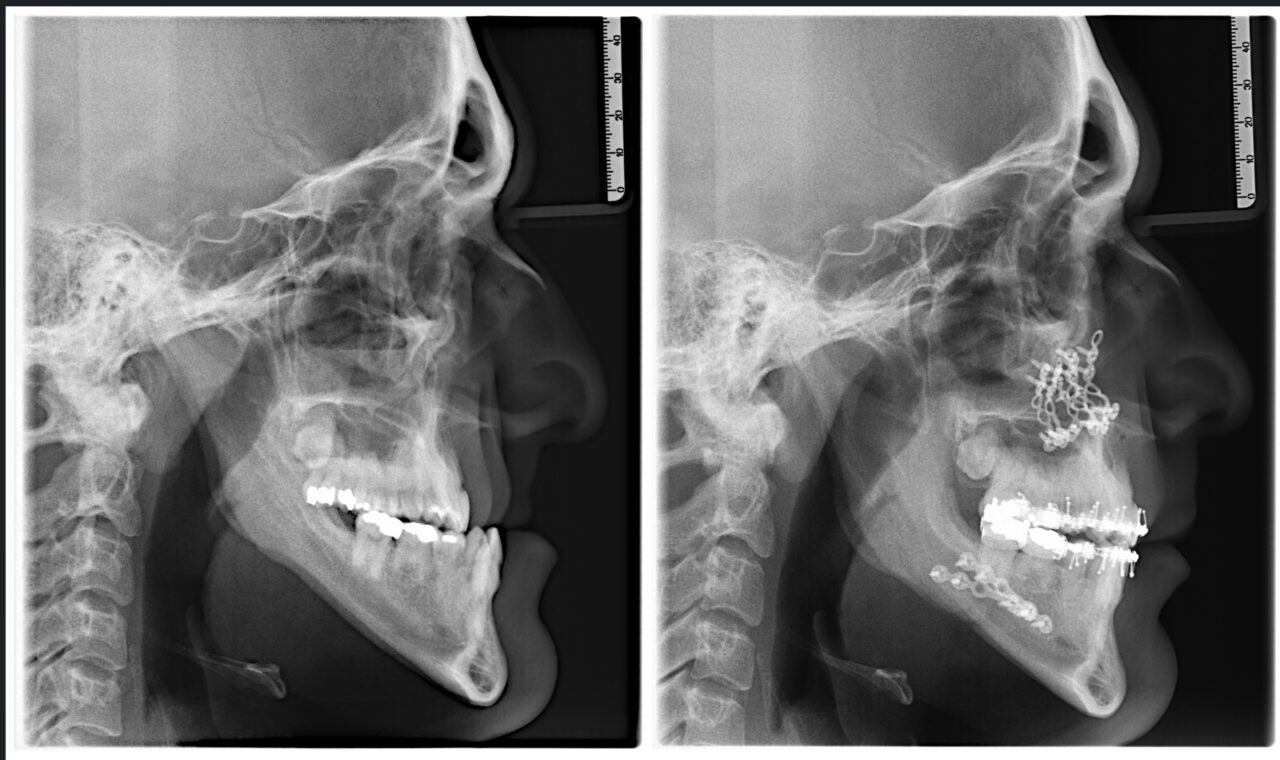

La cirugía ortognática consiste en realizar osteotomías (cortes en el hueso) en los maxilares para poder movilizarlos en la posición planificada. La nueva posición se fijará mediante miniplacas y/o tornillo de titanio para mantener su posición.

El diagnóstico digital mediante escaneado 3D de los dientes y el estudio radiográfico tridimensional con tomografía computarizada (TC ó CBCT) de los maxilares determina el grado de desviación ósea. Si la deformidad dento-esquelética afecta a la estética facial, a la función masticatoria o a la salud articular de la ATM (Articulación Temporomandibular), la cirugía ortognática es la opción indicada.

- Planificación virtual de la cirugía con la ayuda de un software específico que integra los registros digitales tomados al paciente (escaneado 3D de los dientes, tomografía computarizada de los maxilares y registros fotográficos) con el fin de fabricar unas guías (férulas quirúrgicas) que ayudarán al cirujano a posicionar correctamente los segmentos óseos.